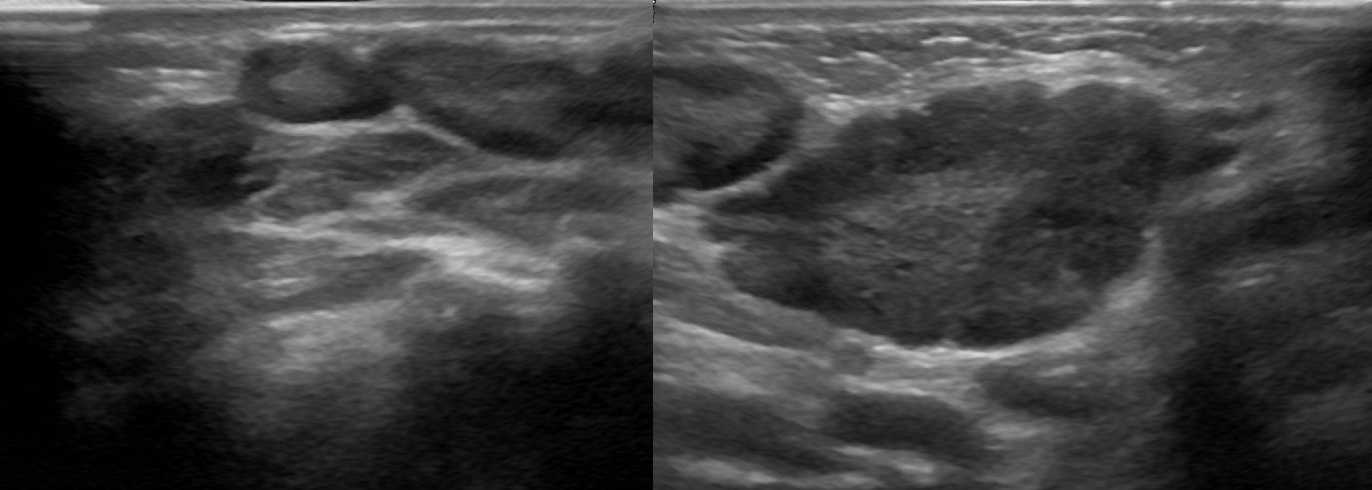

Рисунок. На УЗИ лимфоузлы увеличены, овальной формы, четкий и ровный контур, эхогенность пониженная, корковая зона несколько расширена, центральный рубчик видно отчетливо; кровоток в воротах усилен, сосуды расположены правильно — расходятся радиально, подкапсульный кровоток не определяется. Заключение: Лимфаденопатия с признаками высокой степени активности.

Рисунок. Ребенок с высокой температурой, ангиной и двусторонней «опухолью» на шее, в общем анализе крови атипичные мононуклеары 25%. На УЗИ передне- и заднешейные лимфоузлы увеличены (максимальный размер 30х15 мм), округлой формы, неоднородные

Обратите внимание, центральный рубчик отлично видно, а кровоток на уровне ворот усилен. Заключение: Лимфаденопатия с признаками высокой степени активности

Большие группы увеличенных лимфоузлов на шее характерны для инфекционного мононуклеоза. Учитывая течение болезни и наличие атипичных мононуклеаров, вероятно, у ребенка инфекционный мононуклеоз.

Рисунок. Женщина жалуется на «опухоль» в подмышке и на локте. Неделю назад повздорила с соседской кошкой. На УЗИ подмышечный (сверху) и локтевые (снизу) лимфоузлы увеличены, округлой формы, выраженная гиперплазия корковой и околокорковой зоны, гиперэхогенный центральный рубчик сохранен; кровоток заметно усилен, сосуды расположены правильно — радиально. Заключение: Лимфаденопатия с признаками высокой степени активности. При болезни кошачьей царапины на месте укуса или царапины образуются небольшие гнойнички и одновременно воспаляются близкие лимфоузлы. Один или группа лимфоузлов увеличиваются в размерах до 5-10 см, становятся болезненными, уплотняются. Через 2-4 недели происходит самоизлечение. Иногда образуются абсцессы и свищи.